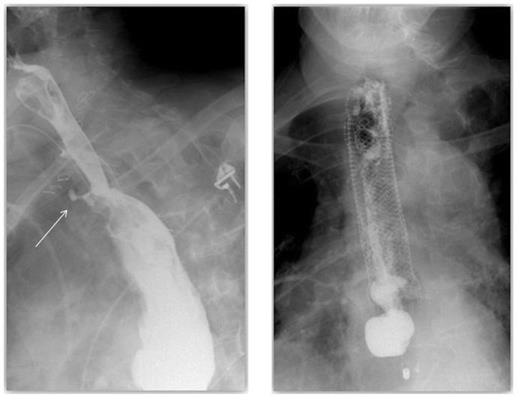

On post-operative day 16 a late pyloroplasty leak was diagnosed on contrast swallow (Figure 3). This presented as a persistent leak of bile stained discharge from the abdominal drain. After failure of initial conservative treatment an attempt to control the leak was made.

The defect at the pyloroplasty suture line was now visible endoscopically and a covered pyloric stent was located appropriately across the defect. Due to proximal stent migration this was unsuccessful in controlling the leak (Figure 4). The patient still had a controlled fistula from the pyloroplasty suture line.

A late pyloroplasty leak diagnosed on contrast swallow & A contrast swallow demonstrating proximal stent migration and evidence of on-going leak